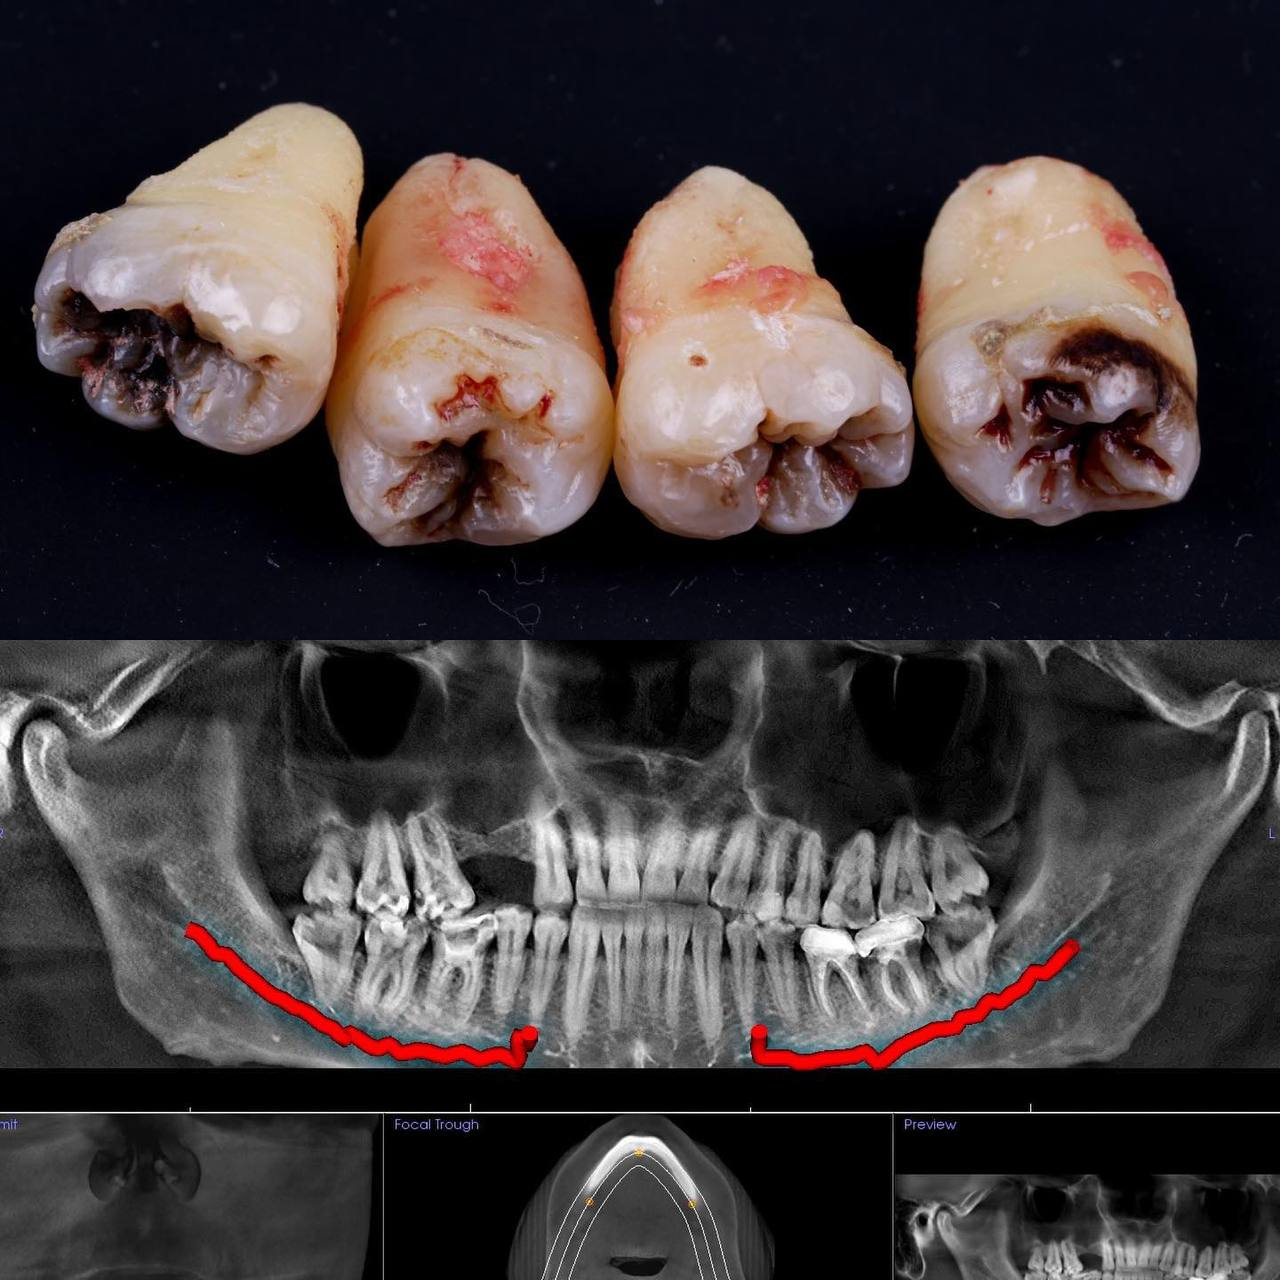

• Полное удаление зуба - если зуб полностью прорезался и имеет сросшиеся корни.

• Отдельное удаление коронки зуба и его корней - если зуб прорезан и корни растут по отдельности.

• Удаление зуба по схеме 1 или 2 с разрезом десен - если зуб прорезан частично.

• Разрез десен, освобождение зуба от близлежащей кости ультразвуком и удаление по схеме 1 или 2 - если зуб не прорезался, но беспокоит.

Вырвать зуб мудрости во Львове можно проще, чем тебе кажется, в Космической стоматологии Драганчука. Начни этот путь с простого шага - первичной встречи с хирургом-стоматологом. На консультации мы сделаем основное - направим тебя на 3D компьютерную томографию, чтобы учесть близость нижнечелюстного нерва (нижние 8-ки) и верхнечелюстной пазухи (верхние 8-ки) и составим план удаления зубов.

Вырвать зуб мудрости во Львове можно проще, чем тебе кажется, в космической стоматологии Драганчука. Начни этот путь с простого шага – первичной встречи с хирургом-стоматологом. На консультации мы сделаем основное – направляем тебя на 3D компьютерную томографию, чтобы учесть близость нижнечелюстного нерва (нижние 8-ки) и верхнечелюстной пазухи (верхние 8-ки) и составим план удаления зубов.